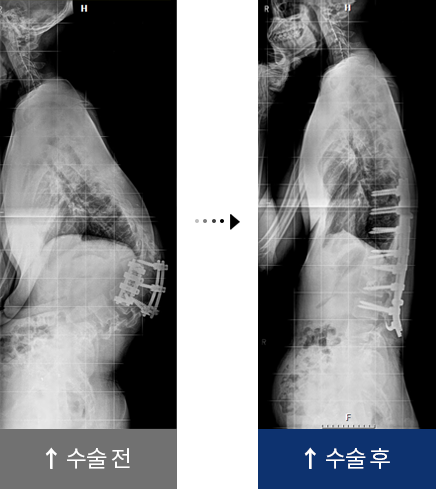

척추 재수술